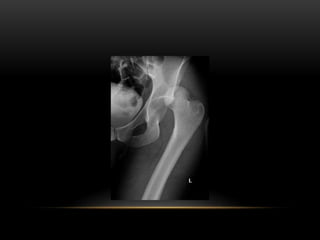

POSTERIOR

DISLOCATION

• Dashboard injury

THOMPSON AND EPSTEIN

CLASSIFICATION

Types Description

i Dislocation with no more than

minor chip #

ii Dislocation with single large

fragment of posterior

acetabular wall

iii Dislocation with comminuted

fragments of posterior

acetabular wall.

iv Dislocation with # through

acetabular floor.

v # through acetabular floor and

femoral head